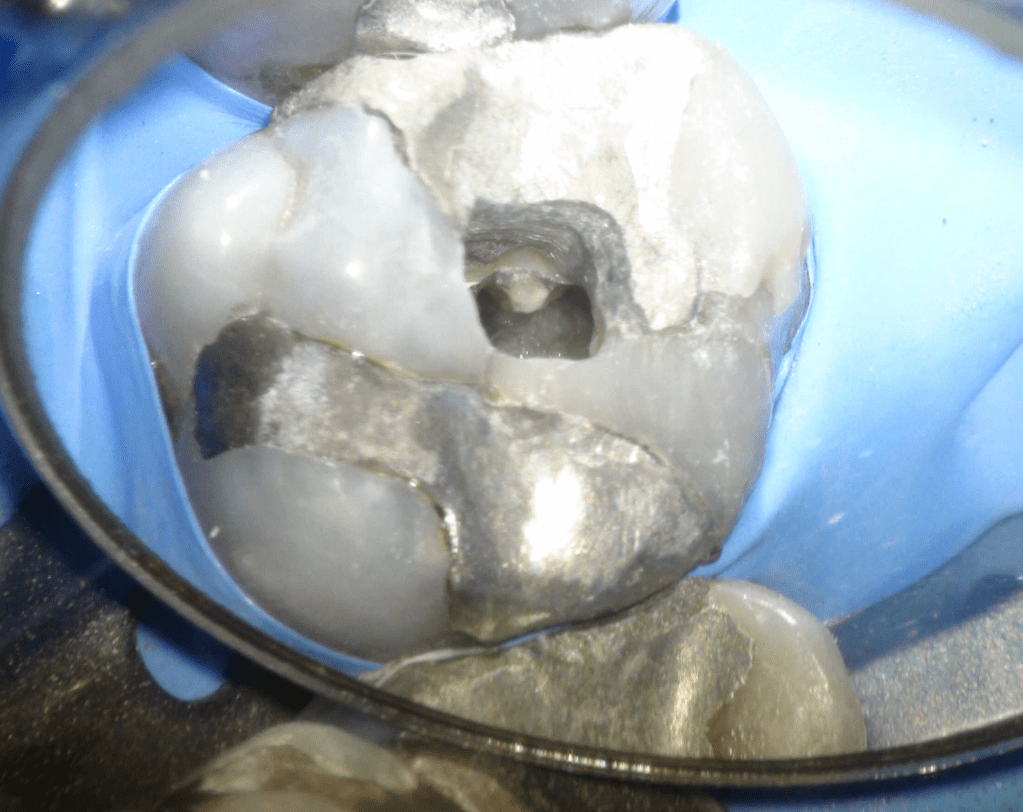

Fisura, remoción amalgama para explorar